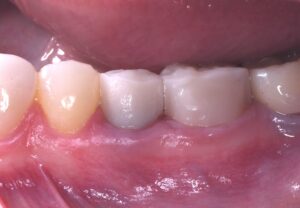

歯茎の位置は変わらることなく補綴をして無事に治療終了しました。若干暗さはありますが、実際お話しして気になることは全くありませんでした。最初のクラウンは不適合で写真でもわかるように隙間が開いてます。今回のものはぴったり適合しています。患者様も大満足。あとは、フッ素を上手に使いながら虫歯にならないようにメンテしていきます。